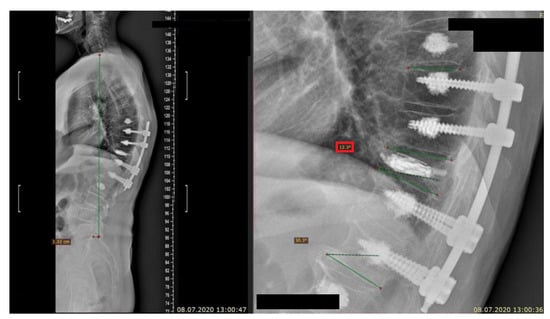

- Adamska, O.; Modzelewski, K.; Stolarczyk, A.; Kseniuk, J. Delayed posttraumatic vertebral body collapse “Kummell disease”. Med. Case Rep. Study Protoc. 2021, 2, e0092. [Google Scholar] [CrossRef]